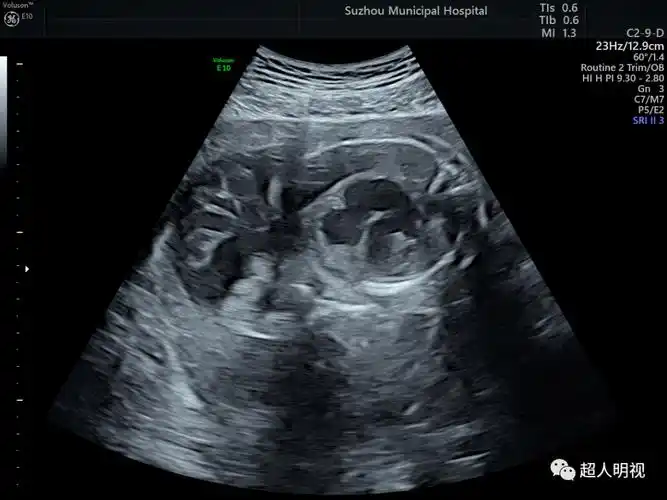

两个病例_胎儿_分析_解剖